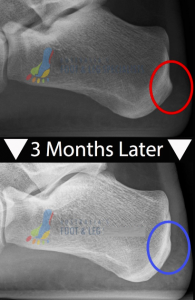

Can I Remove a Heel Spur without Surgery?

Bones once formed are for life but this doesn’t mean your heel pain is. Unfortunately bone spurs don’t spontaneously re-absorb when you remove the excessive tendon pull, but it does stop your heel spur from growing in size. It’s also important to note that as long as you relieve the strained muscles you can relieve your pain so physical removal of the heel spur is not necessary in most cases. Interestingly we have seen cases where we’ve been able to catch heel spurs early, while they’re not fully formed bone more of a cartilage type substance and that can re-absorb if you relieve the muscular tension. An example of this heel spur re-absorption over 3 months is shown on the x-rays of the same patient after treatment below (individual results will vary):